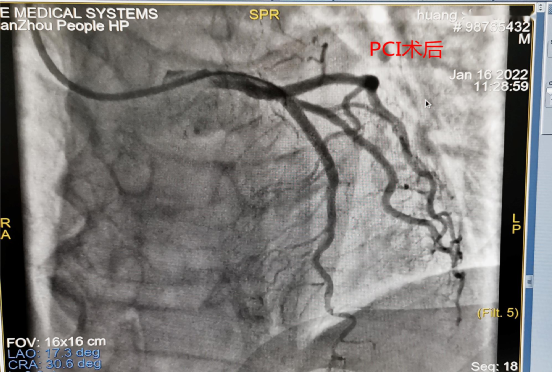

医生边询问病史边行床边心电图,并上传到胸痛中心微信群。拨打胸痛中心一键启动电话行远程会诊,经会诊后确诊STEMI(前壁),建议排除禁忌后,予第三代溶栓药瑞通立全量静注溶栓治疗。医疗救治、辅助检查、医患沟通紧张有序进行,确诊10分钟内予负荷量双抗血小板、稳定斑块治疗,并联系120转胸痛中心治疗。在诊治过程中,患者突然意识丧失,呼之不应,抽搐、小便失禁,心电监护示室颤,考虑心脏骤停,立即予心脏按压、呼吸囊辅助通气、双向波200J电除颤、静注肾上腺素等抢救治疗,约4分钟后患者恢复窦性心律,颈动脉可触及搏动,恢复自主呼吸,血压90/50mmHg,有溶栓禁忌症,边抢救边转送到总院人民医院胸痛中心治疗。通过区域协同救治机制,院内院外搭建绿色通道,绕开急诊科及CCU病房,直达介入室予PCI治疗,术中见前降支中段狭窄>90%,向前TIMI血流2级,11:08导丝通过,予植入支架1枚。患者住院治疗5天,病情稳定,未出现并发症,康复出院。